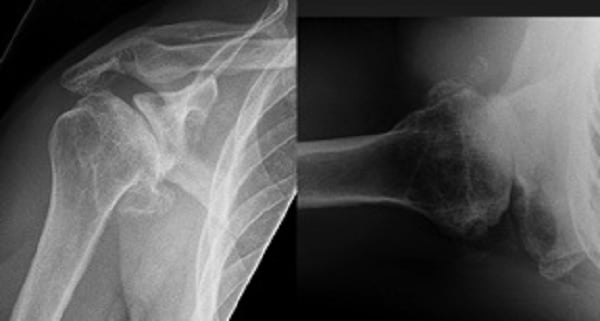

Radiographs of the right shoulder showed end-stage glenohumeral osteoarthritis with significant glenoid retroversion (B3 Walch classification) [1] and posterior humeral head subluxation (Fig. 1). A computed tomography (CT) scan to assist with preoperative planning showed excessive glenoid wear, with 25° of retroversion (Fig. 2).

Figure 1: Anteroposterior (AP) (left) and axillary (right) radiographs of the right shoulder

demonstrate glenohumeral osteoarthritis with a B3 glenoid deformity.